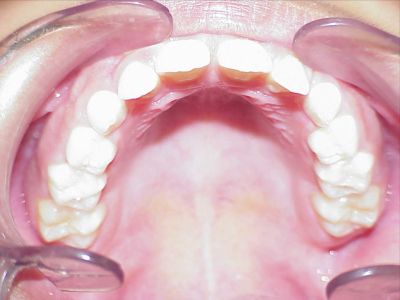

Voor behandeling

Na behandeling